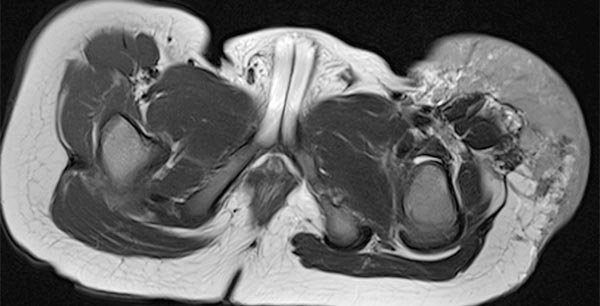

Die koronare, T2-gewichtete, fettgesättigte MRT zeigt den Tumor in der linken Leiste homogen stark hyperintens (13. Lebensmonat) und klar solide. Nebenbefundlich die durchnässte Windel, ebenfalls mit hoher Signalintensität.

Gleiche MRT-Sequenz, koronare Schichtführung. Der Tumor liegt nicht nur epifaszial, sondern zeigt auch eine geringe Ausdehnung nach subfaszial unter die Fascia lata in die Glutealmuskulatur. Damit klar infiltratives Verhalten.

Auch in der axialen Schichtführung der MRT (T2-gewichtet, fettgesättigt) ist die Infiltration der Muskulatur durch die Raumforderung gut dargestellt. Auch Hämangiome können als vaskuläre Tumoren eine solche Infiltration aufweisen, ohne dass sie maligne sein müssen.